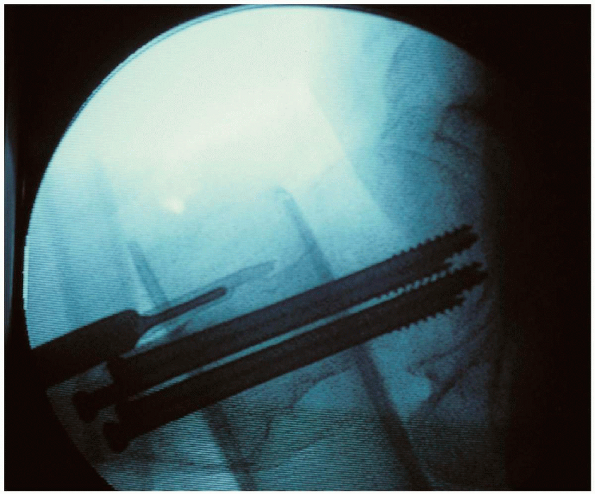

![]() |

FIGURE 21-19.

Three guide wires are inserted into the femoral neck and head under image intensification. The guide wires should all be parallel and oriented in an inverted triangular configuration, with one wire inferior and two wires superior. This orientation provides the most mechanically secure fracture fixation. |

guide wires are inserted into the femoral neck and head under image

intensification. A guide wire can be placed anterior to the femoral

unnecessary. The guide wires should all be parallel and oriented in an

inverted triangular configuration, with one wire inferior and two wires

superior; this orientation provides the most mechanically secure

fracture fixation (Fig. 21-19). The guide wires

prefer a freehand technique. The inferior wire is placed adjacent to

the inferior neck cortex to resist varus displacement,

while one of the two superior wires is adjacent to the posterior femoral cortex to resist posterior displacement.

These guide wires should be spaced apart to maximize fixation stability and inserted into the dense subchondral bone. Acommon pitfall during cancellous lag screw insertion is to place the